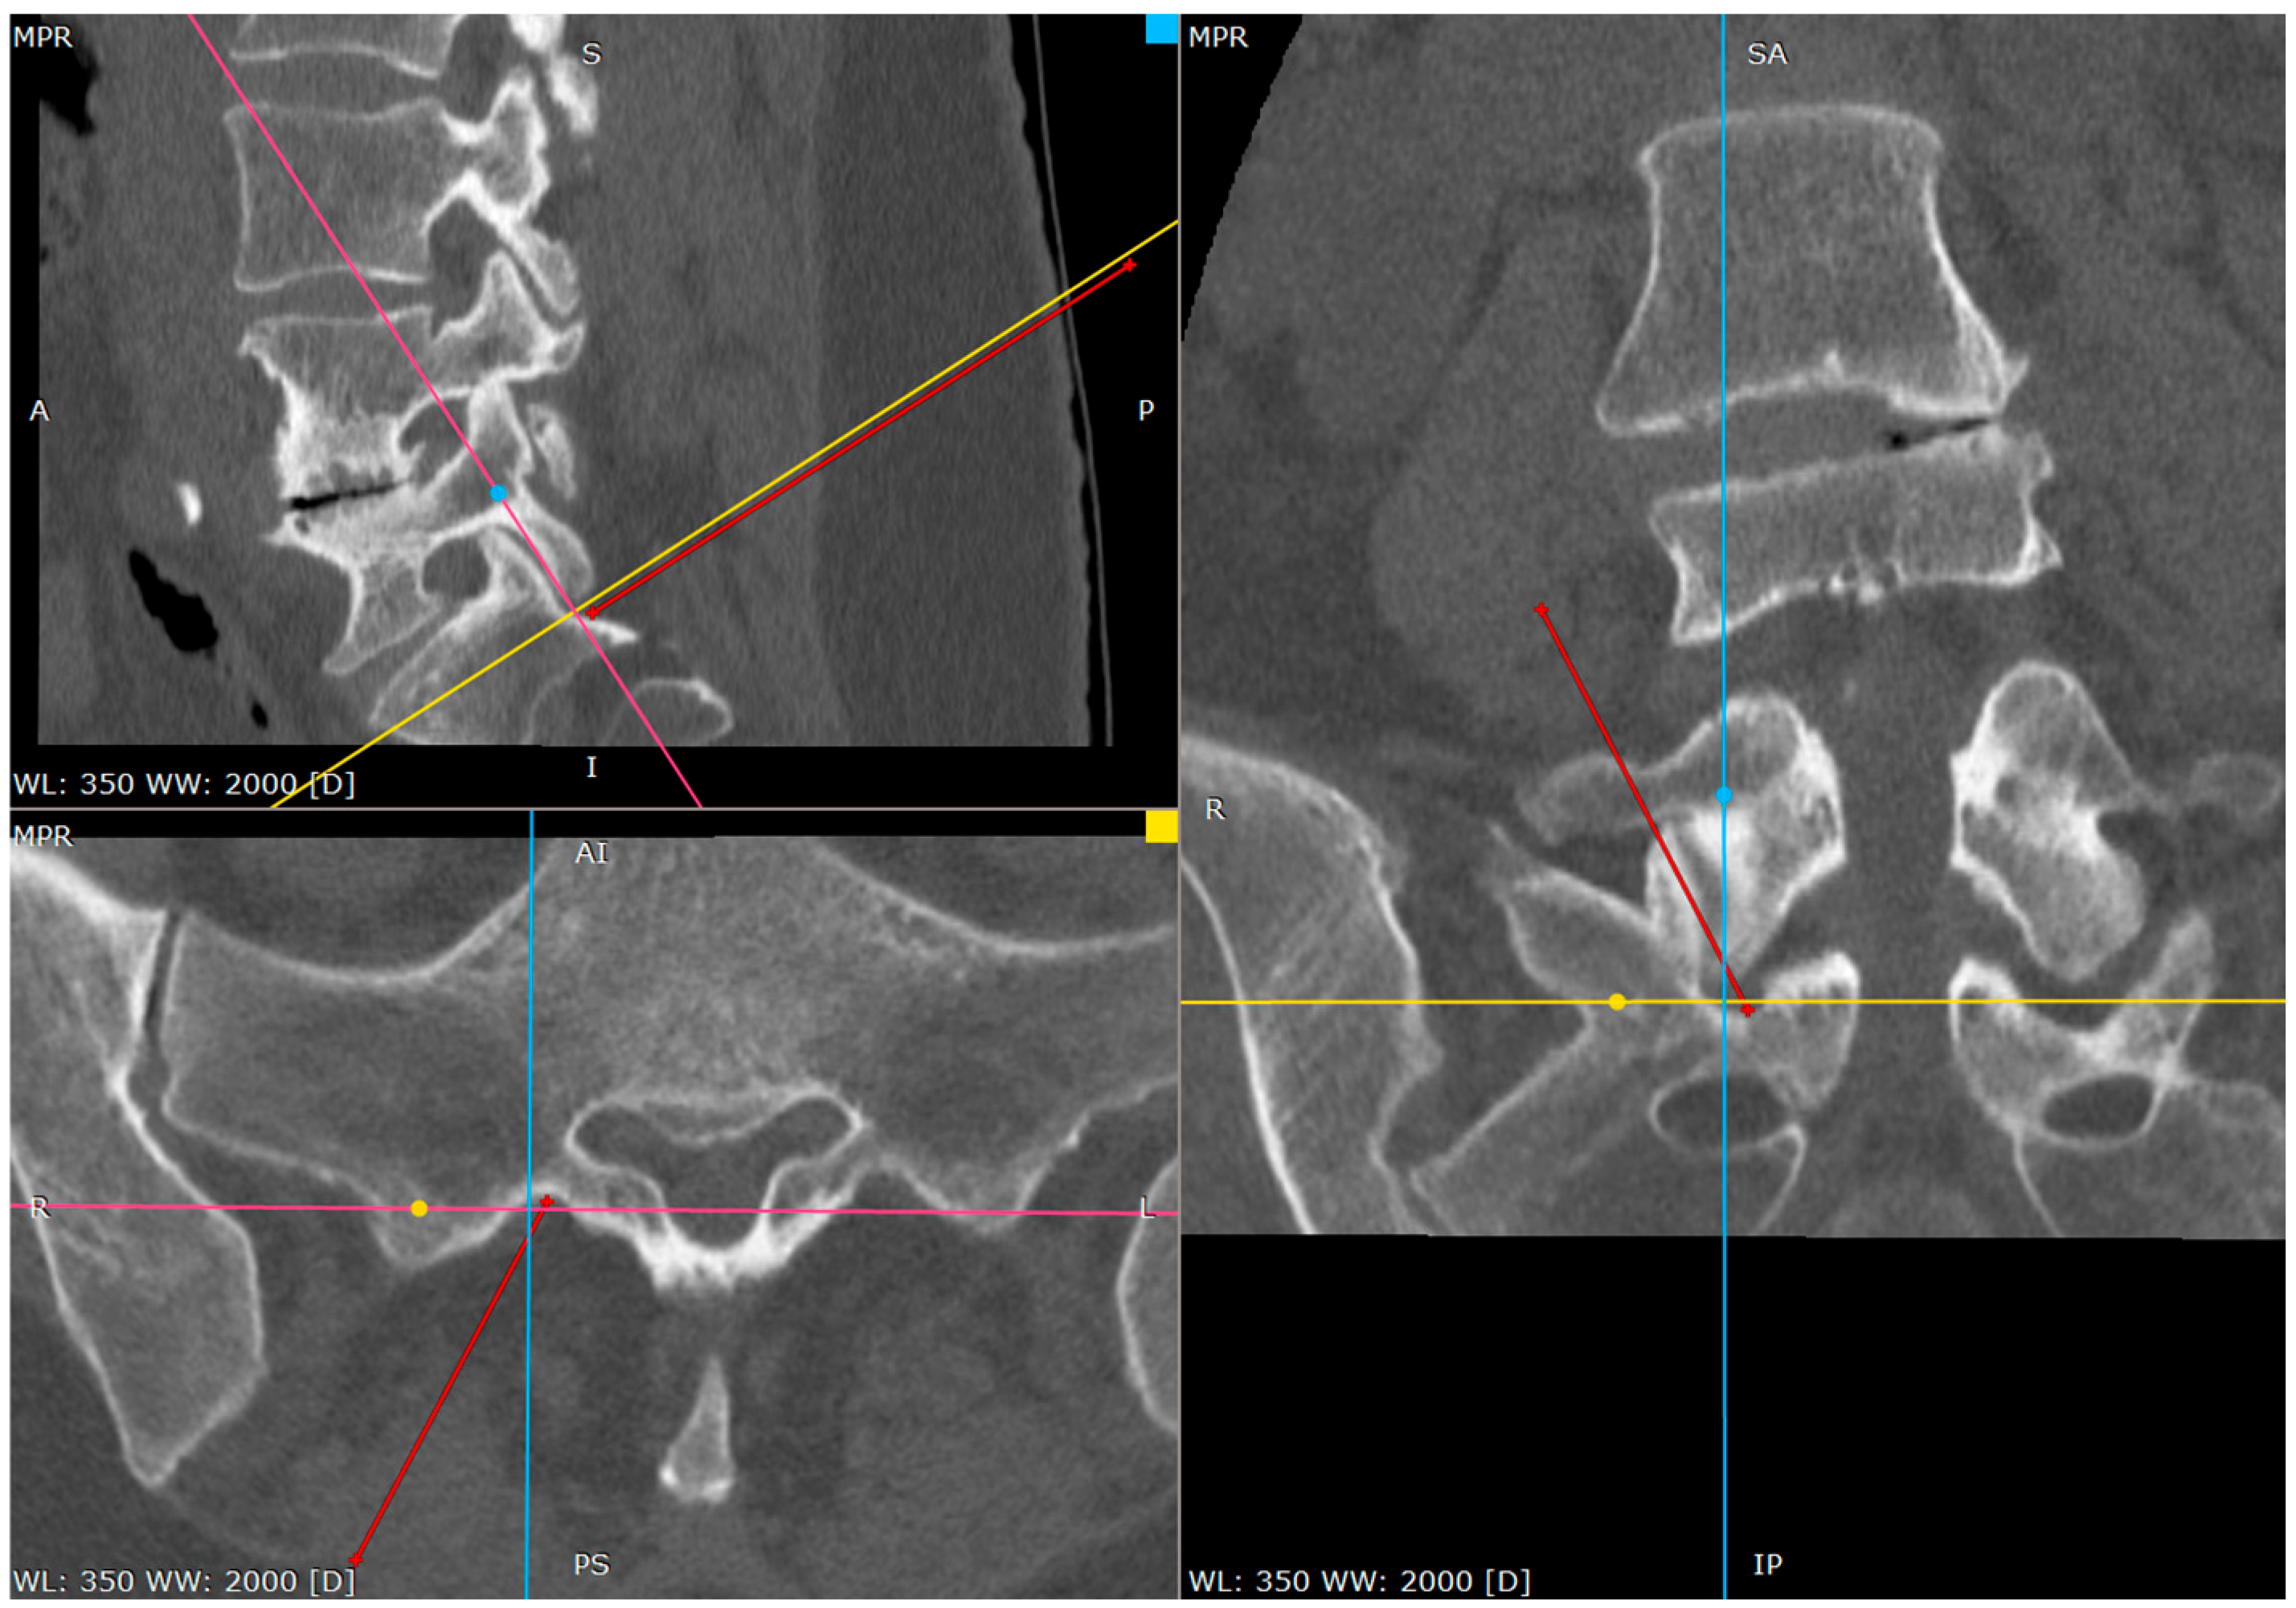

The primary target point for the needle introduction is the lower part of the facet joint or the caudal part of the articular surface of the S1 superior facet (Figure 2 and Figure 3).

It is safer to aim at the lower part of the facet joint, because it is an easily identifiable structure in any anatomical variation.

Figure 2. The primary target point—the inferior part of the facet (a CT tri-plane reconstruction).